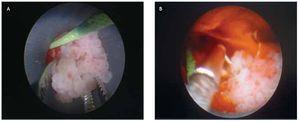

La cirugía fue reportada sin incidentes ni accidentes. En un tiempo de una hora 20 minutos (Figuras 4 y 5). Con una estancia intrahospitalaria posoperatoria de cuatro días. La sonda de nefrostomía del tracto percutáneo se retiró al tercer día.

Figura 5. A) y B) Imágenes de la cirugía con abordaje percutáneo con extracción de fronda tumoral en frío con pinza de cuerpo extraño, resección y hemostasia de base del tumor con resectoscopio bipolar.